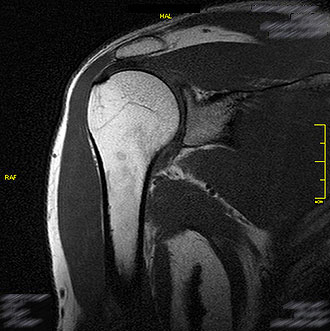

Die MRT Schulter ist die Standarduntersuchung bei Schmerzen, Bewegungseinschränkungen oder nach Verletzungen.

Im Kernspin Zentrum Köln lassen sich Schultersteife (Frozen Shoulder), Traumafolgen, Kapselrissbildungen, Schulterverkalkungen oder Risse in der Bizepssehne genau darstellen.

Gerade bei unklaren Beschwerden liefert die MRT entscheidende Hinweise, um eine Operation zu vermeiden oder optimal vorzubereiten.